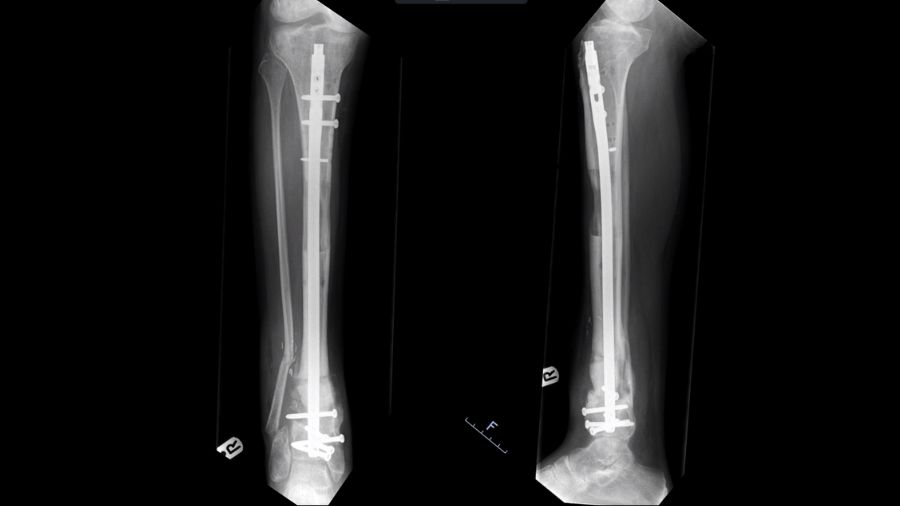

The lengthening nail is a new development that could prove to be a game changer and is worth mentioning in this context. It employs the same biomechanics and bone physiology as the Ilizarov method, but with purely internal fixation.

With plate assisted bone segment transport (PABST), a plate holds the limb out to length, which is also what a stacked ring fixator does. In the ring fixator, a middle segment moves to drag the piece of bone down to fill the gap, but here, it’s the lengthening nail that does the moving of the bone. It moves the middle segment from the top to the bottom at the right pace, so that distraction osteogenesis causes new bone to form in the gap. It works in the same way as a frame, but crucially it is not an apparatus on the outside of the leg with the pins dragging through the skin.

A real advantage of this method is that it makes it much easier to deal with swelling, which can be a problem. Because all the stability is internal, patients can wear pressure garments and physiotherapists can get at their leg to help manage the swelling, making the patient journey better.

The transport nails have also reduced the treatment times required. The amount of time spent in the transport phase is reduced because nails can be potentially distracted faster— distraction osteogenesis can happen at a rate of up to 1.25mm a day with fewer breaks for things like pin site infections. You therefore reach the last stage of treatment, managing the docking site, sooner. The patient is still waiting for the fracture to heal and having physiotherapy, but they are not lying in hospital or having to visit as often, which is another improvement. With the lengthening nails, the patient's contact with the hospital and the burden of being a patient is considerably reduced.